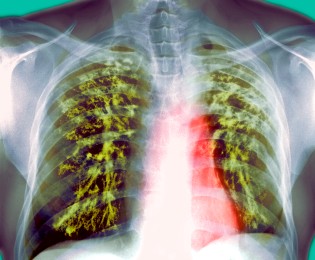

One of the most valuable things I have learned so far in my year of service have been the distinctions that exist between the realms of public health and medicine. Even though these two disciplines often go hand in hand, there are very real distinctions in focus that can have a very real effect on the health of patients. At the Squirrel Hill Health Center, one of these distinctions has become quite clear in patients that have tuberculosis (TB). All new patients at the health center have a screening exam, either a skin test or a blood test to determine if they have been exposed to tuberculosis. If the test comes back positive, they are sent for a chest x-ray and other symptoms are taken into account to determine whether the patient has an active or latent form of infection.